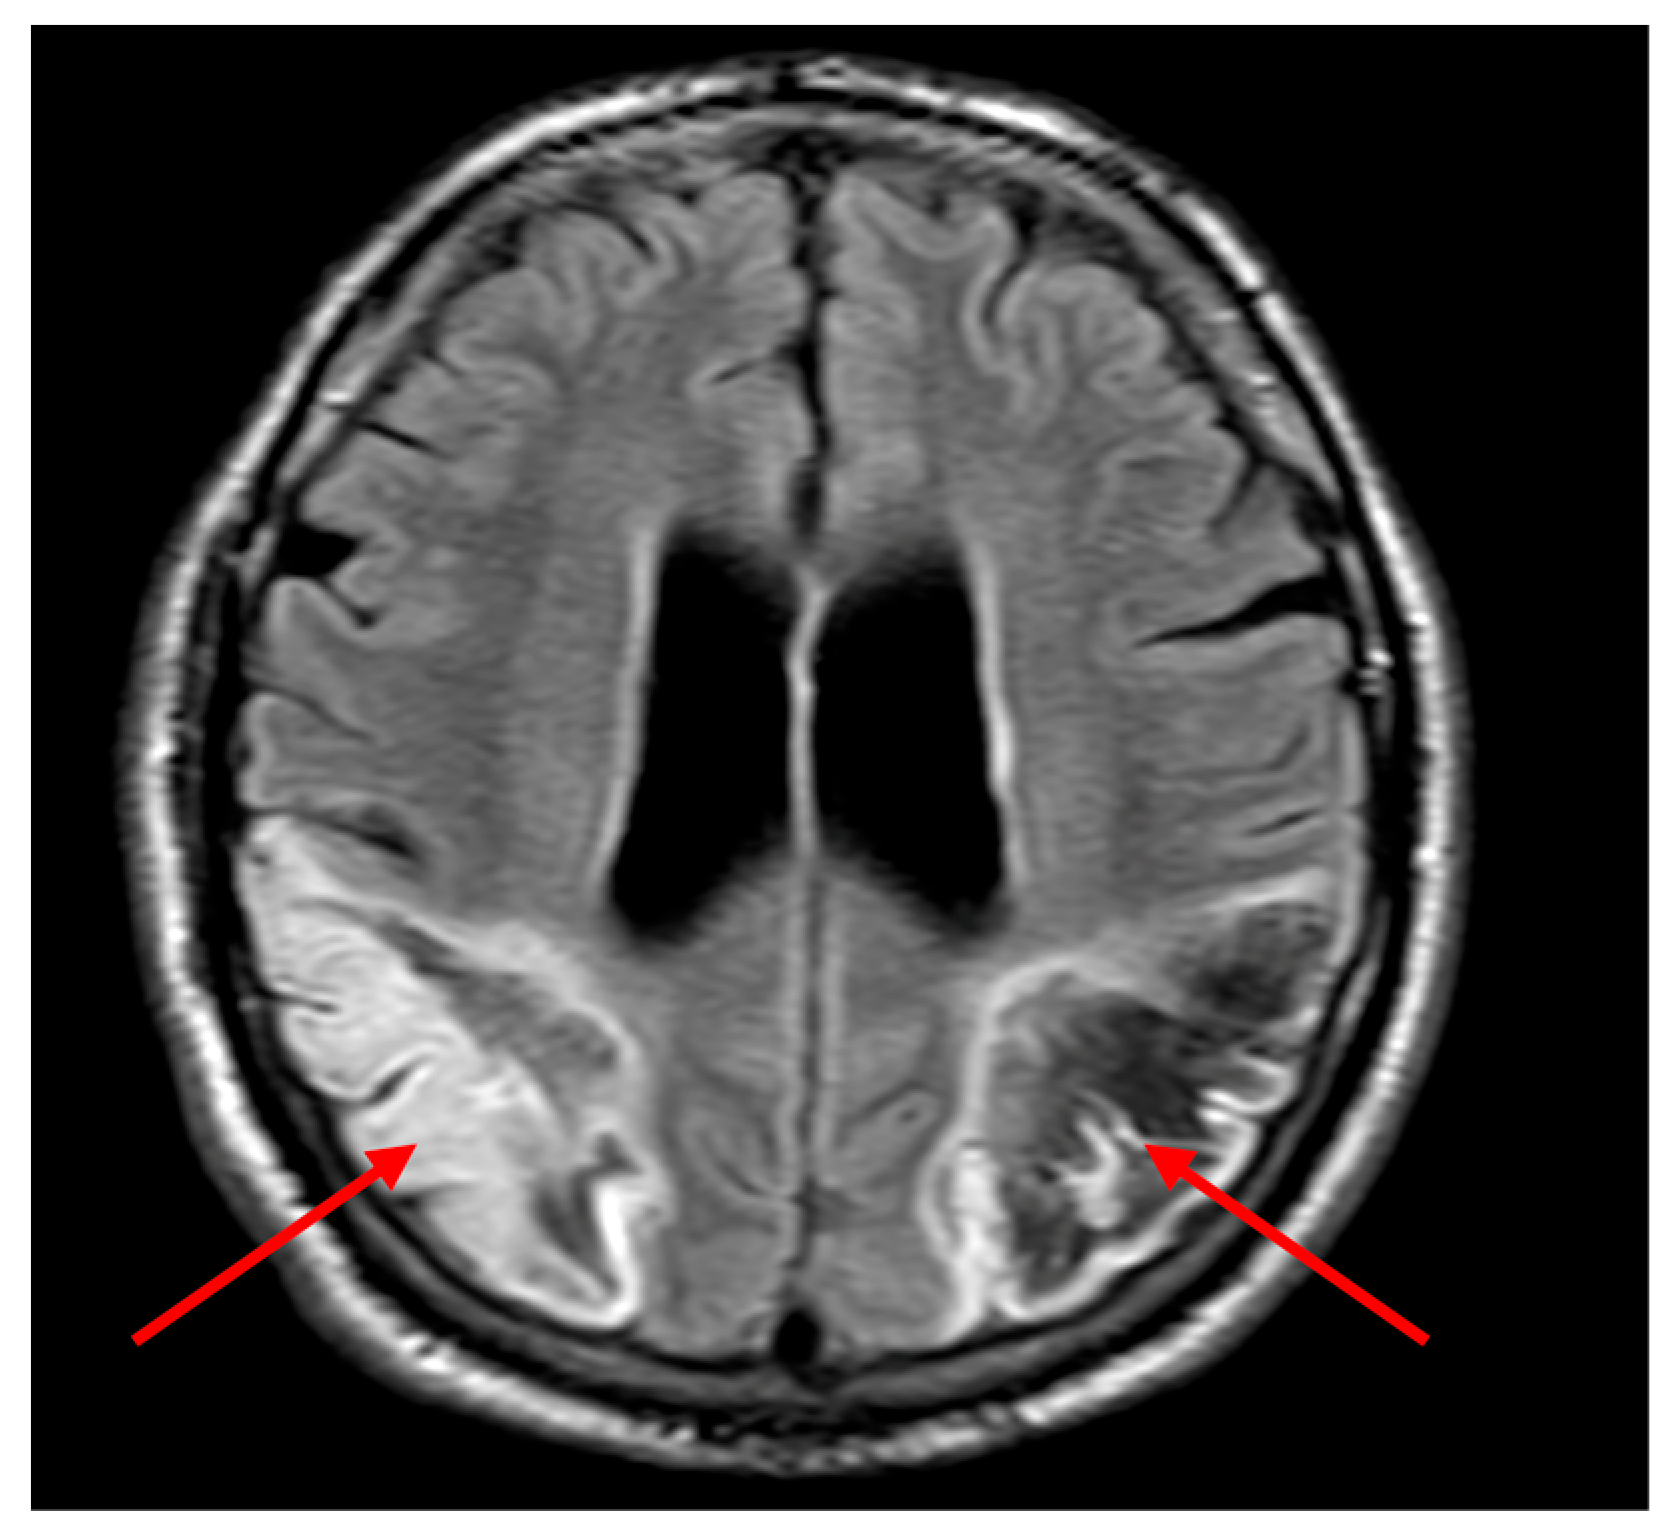

Non-contrast computed tomography (CT) of the head demonstrated an evolving acute infarct in the right posterior parieto-occipital region with poorly defined hypodensity, white matter oedema, and mild mass effect (Figure 1). Apixaban was immediately withheld, and aspirin was commenced after coagulation screening. MRI brain was requested to rule out a space-occupying lesion.

Figure 1. Non-contrast axial Computed Tomography (CT) of the brain showing an evolving infarct in the right posterior parietal lobe (white arrow), characterised by ill-defined hypodensity and loss of grey-white matter differentiation, consistent with acute ischaemic stroke. There is no significant midline shift or haemorrhage noted.